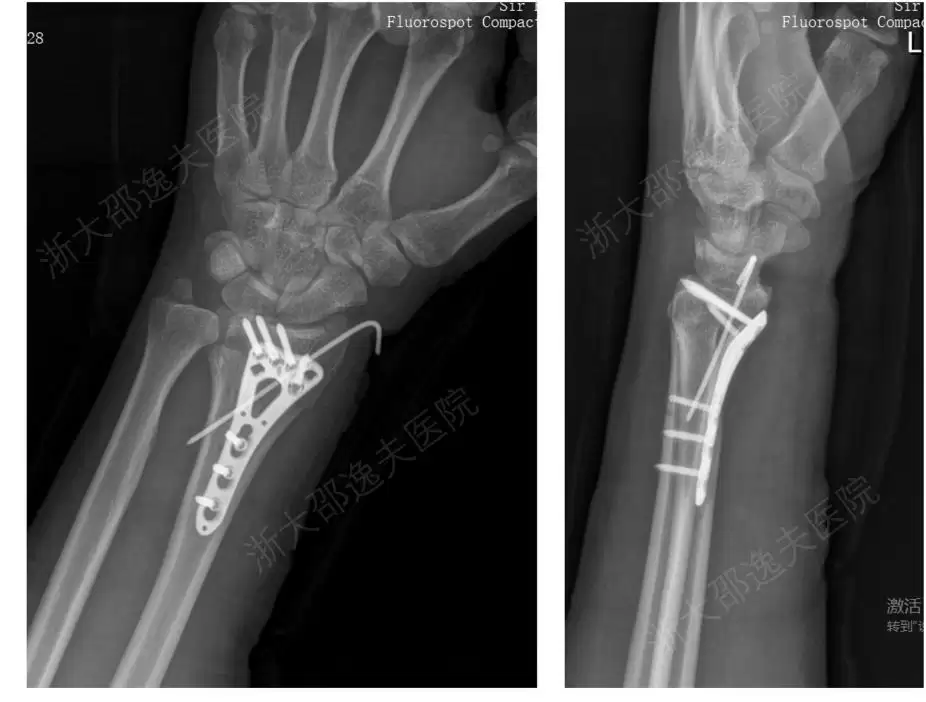

“骨 02”的临床价值也已在全国各中心 150 余例受试病例中得到验证。其中,一位年轻工人因外伤导致腕部桡骨远端粉碎性骨折,传统治疗方案需大切口植入钢板螺钉(见图 2),不仅创伤大、存在肌腱粘连或神经损伤风险,且需术后一年行二次手术取出。应用“骨 02”黏合技术,团队仅通过一个 2~3 厘米的微创切口注入“胶水”材料,短短 3 分钟内即完成了粉碎骨块的精准黏合与固定。术后 3 个月随访显示,患者骨折愈合良好,无并发症,腕关节功能完全恢复(见图 3)。